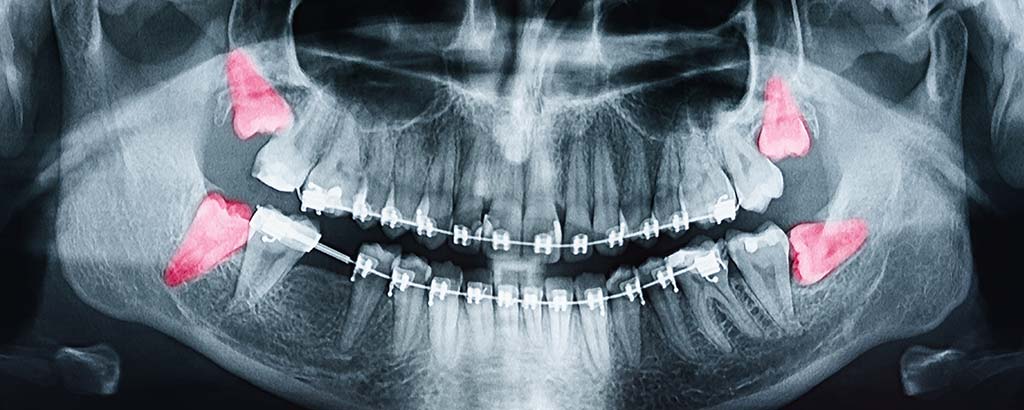

An average adult mouth is designed to hold around 28 teeth comfortably but most adults end up with 32 teeth. These additional four teeth are called wisdom teeth, (AKA) third molars. The reason that some adults grow wisdom teeth is because throughout evolutionary history the human jaw has become smaller and smaller. Because of this the wisdom teeth become blocked or impacted by the other teeth around them. This can become extremely traumatizing. If the wisdom tooth partially erupts, food can get trapped in the tissue surrounding the tooth, which can lead to bacterial growth and possibly serious infection.

Why Remove Wisdom Teeth as a Young Adult?

By removing wisdom teeth when a patient is a young adult, Drs. Hamidzadeh and Church are able to prevent potential healing problems. When a person reaches the age of their mid thirties there are much higher risks for wisdom teeth removal. The best time to remove wisdom teeth is generally between the ages of fifteen to eighteen years of age.